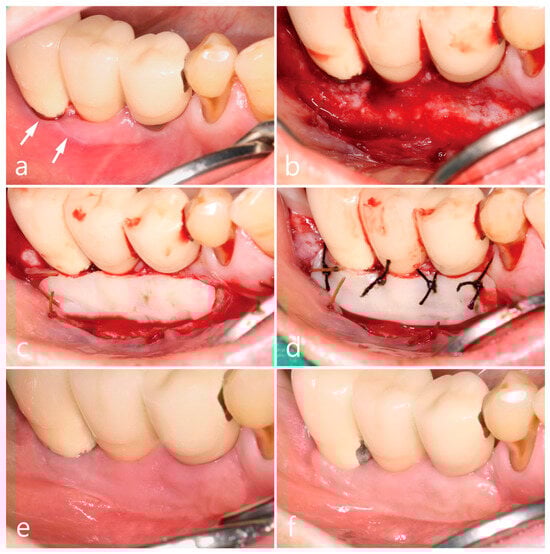

2. Case Presentation

2.1. Mandibular Right Posterior Region

2.2. Maxillary Left Posterior Region

2.3. Mandibular Left Posterior Region